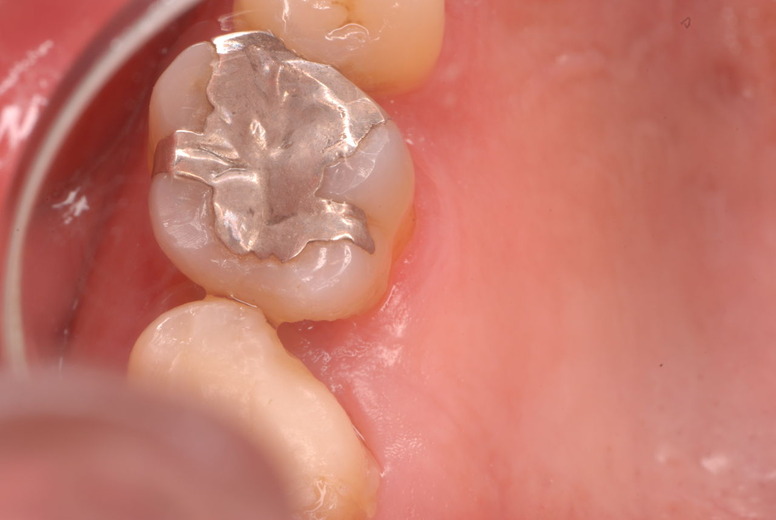

色々不満な入れ歯です。

発音や見える金属が気になるようです。